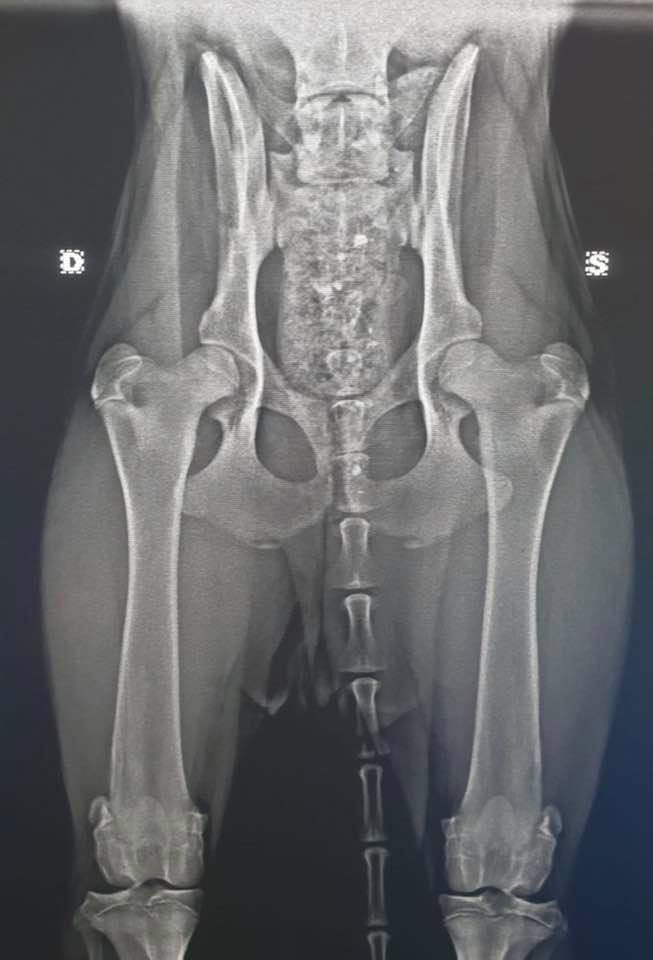

Wer hier auf dem Bild sagt, das geht doch noch, der solle sich doch mal hinsetzen und noch zu den vielen Punkten, nehmen wir mal den Kreuzbandriss als Beispiel an, folgendes hinzurechnen. Kostender OP 2.000 + 4facher Satz an Gebührenordnung + evt. Not Op am Wochenende + Tagesaufenthalte für eine Woche in der Klinik inkl. Medikamentensetzung und Heilmittel, Wundversorgung und Physiotherapie, nach Entlassung, dreimaliges vorstellen inklusiver Nahtversorgung, Medikamentgaben für zuhause und Verordnung von wochenlanger Physiotherapie usw.